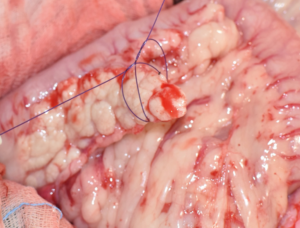

La tomografía computarizada (TC) puede ser particularmente útil en la investigación de insulinomas, puesto que el gas en el tracto gastrointestinal no supone una limitación y es una prueba más sensible en la identificación de pequeñas lesiones, aunque para ello se suele necesitar la TC de fase dual. El insulinoma se caracteriza por presentar una imagen de nódulo hipoatenuante con un gran refuerzo, únicamente en la fase arterial del estudio (halo de contraste alrededor del nódulo) y no en otras fases (imagen 1).

Imágenes 4A – 4K. Secuencia de imágenes quirúrgicas en un perro (con las imágenes del TC), durante una pancreatectomía total del lóbulo izquierdo y cuerpo del páncreas (usando la técnica de “guillotina” sutura/fractura con el nudo de Miller modificado) y resección de NNLL centinelas, por insulinoma en el cuerpo del páncreas.

Imágenes 5A – 5H. Secuencia de imágenes quirúrgicas en un perro (con las imágenes del TC), durante una pancreatectomía total del lóbulo derecho y parte del cuerpo del páncreas (usando la técnica de “guillotina” sutura/fractura con el nudo de Miller modificado) y resección de NNLL centinelas, por insulinoma en el lóbulo derecho del páncreas.